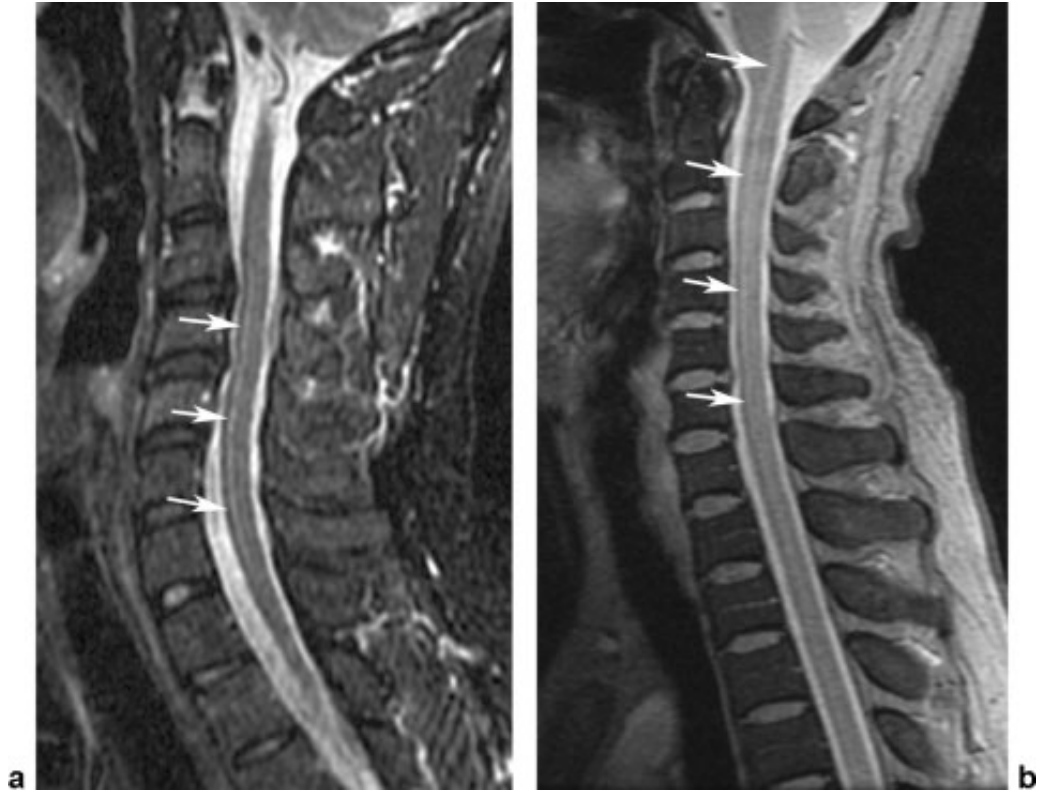

截断伪影常见于 MR 信号强度突然变化的组织界面,如脂肪-肌肉和脊髓-脑脊液界面,可能导致脊髓内出现虚假高信号,易被误解为脊髓空洞或损伤。通过校正编码方向等方法可改善。